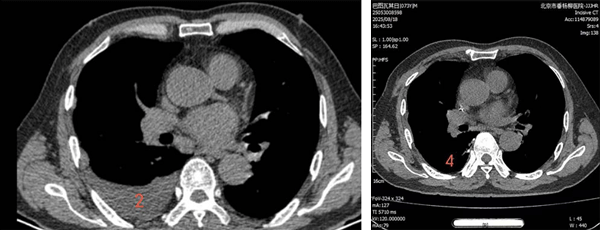

术前

1、胸腔积液(肺窗)2、胸腔积液(纵隔窗)